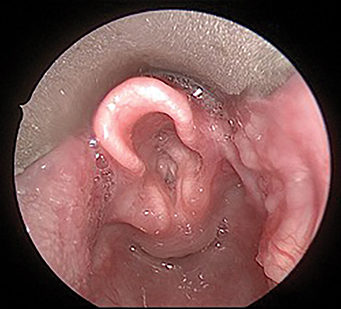

The “face” of head and neck cancer in 2020 has changed, with fewer tobacco-related cancers and an increasing number of HPV-related oropharyngeal, thyroid, and skin cancers. The HPV-related oropharyngeal cancer epidemic is associated with a growing cohort of long-term survivors. Deintensification of radiation and/or chemotherapy can be accomplished with transoral surgery in patients without evidence of extranodal extension and clear margins, all being studied in globally initiated multidisciplinary clinical trials. Surgeon-initiated trials include elective versus therapeutic neck dissection in node negative oral cavity cancer and the E3311 transoral surgery study, with a postoperative radiation deintensification arm.